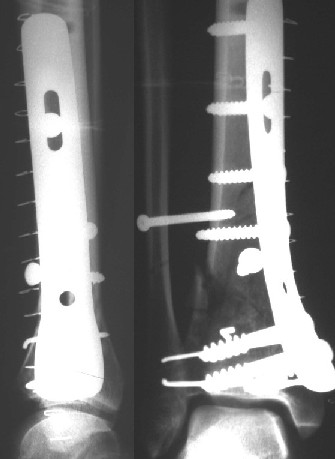

Уважаемые коллеги!Поступила пациентка 40лет, псевдоартроз Н/3 большеберцовой кости, оперирована 1,5-а года назад по поводу перелома ПИЛОНА в Австрии, травма горнолыжная.

после остеосиннтеза |  05.07.04 |  12.04.05 | Пластина удалена через 4-е месяца (миграция винтов), полимерная повязка на 2-а мес. Беспокоит деформация голени,укорочение 1-1,5см, боли незначительные, движения в г/стопном суставе в полном объёме, ходит с полной нагрузкой на ногу, подвижность в переломе не определяется. Одномоментное исправление деформации, костная пластика (chronOS)+ пластина? Аппаратная коррекция, затем пластина? Аппарат? Прошу Ваших советов. С Уважением А.Миронов